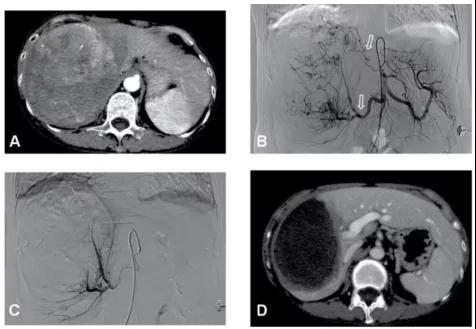

图1、病例54岁,肝右叶5.5×5.4cm肝癌(左图),行TACE+消融肿瘤完全坏死并缩小(右图),现患者已生存14年。